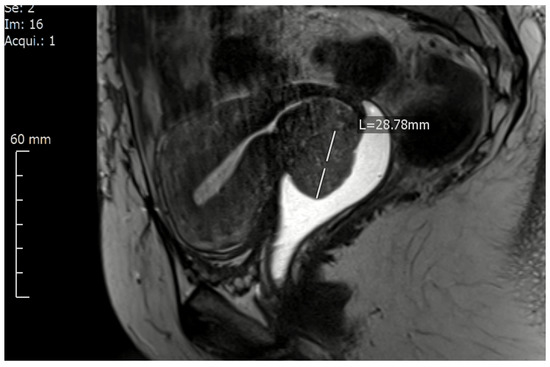

- Tumours with a big volume but without macroscopic infiltration in the vaginal vault or obvious infiltration in parametrium/paracolpium (FIGO Ib2, Ib3): these tumours demand a resection of a longer vaginal vault to be able to close the vaginal cuff beneath (caudal) from the tumour to avoid any spelling of tumour cells and any contamination of the abdominal cavity. In these cases and because of the curved and anteflexed shape of the upper vagina, tumors with ventral localization demand the resection of longer vagina cuff comparing with tumors from the same size and stage but with dorsal localization (Figure 1).

Figure 1. A magnetic resonance imaging of cervical cancer location on the ventral lip of the cervix (FIGO IB2) presented using a contrast agent in the vagina. - (2)

This classification takes too into account the location of the cervical lesion in the cervix, which plays an important role in the surgical decision about the resected length of the vaginal vault during the radical hysterectomy. The classification distinguishes, therefore, between tumours locating on the ventral (anterior) and tumours locating on the dorsal (posterior) cervical lips in FIGO IB-stage. This is because of the fact that the resection of a longer vaginal wall ventrally, which is, of course, the case with tumours locating at the ventral cervical lip (Figure 1), is anatomically more challenging and demands at least the preparation and isolation of the proximal aspects of paracolpium to be able to resect a longer vaginal vault without injuring the inferior hypogastric plexus and the vaginal blood supply.